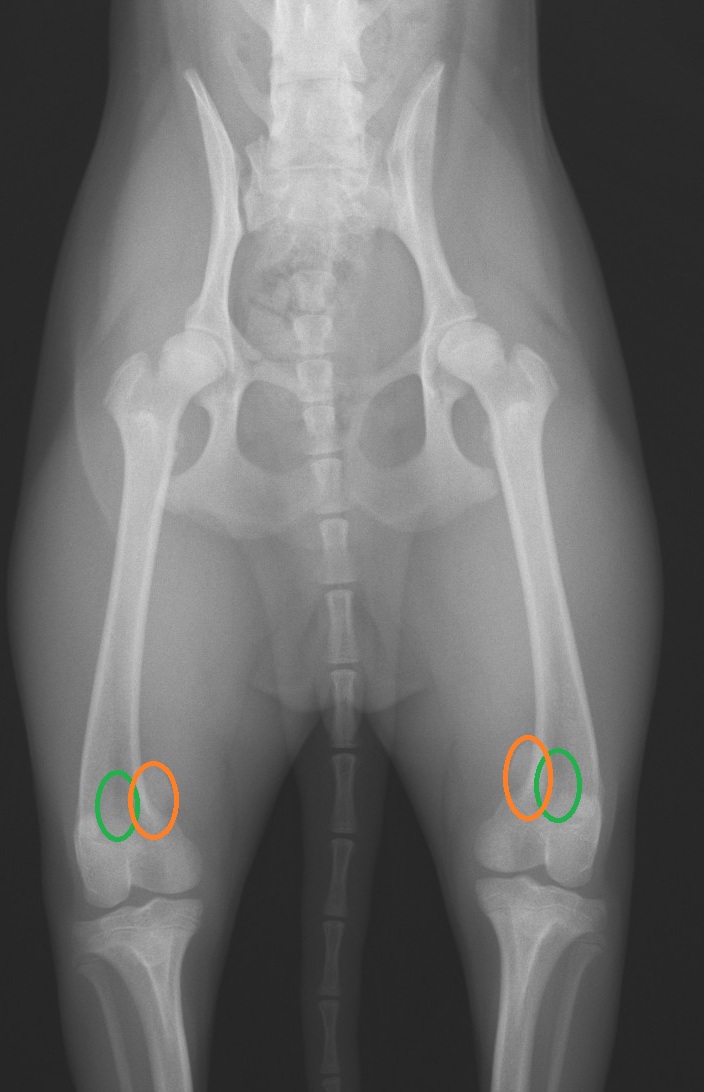

正常な位置は緑の丸の位置、

でも、膝蓋骨が

オレンジのところにあるので、

内側に脱臼していることが、

診断できます。

触診で診断できますが、

正確な診断には

レントゲン検査が必須です。